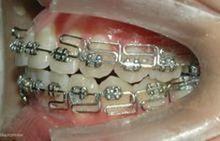

(1)方絲弓矯治技術托槽

方絲弓矯治技術口內相(2)Begg矯治技術托槽